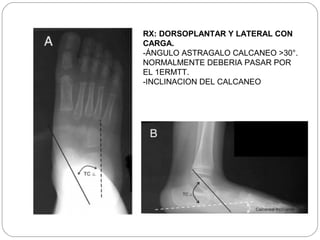

RX: DORSOPLANTAR Y LATERAL CON

CARGA.

-ÁNGULO ASTRAGALO CALCANEO >30°.

NORMALMENTE DEBERIA PASAR POR

EL 1ERMTT.

-INCLINACION DEL CALCANEO

ASTRAGALO 3-A´s Abajo, Adelante,Adentro ALTERACION FUNDAMENTAL ARTICULACION SUBASTRAGALINA

RX: DORSOPLANTAR YLATERAL CON CARGA. -ÁNGULO ASTRAGALO CALCANEO >30°. NORMALMENTE DEBERIA PASAR POR EL 1ERMTT. -INCLINACION DEL CALCANEO